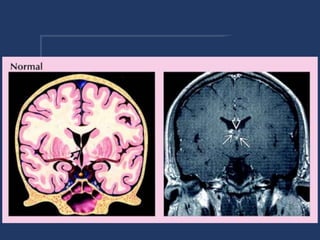

CAVUM VELUM INTERPOSITUM

• cystic dilatation of cistern of Velum

interpositum

• k/a - cavum velum interpositum,

cavum velum triangulare, cyst of the

velum interpositum

• located

• midline between the lateral ventricles

• below the fornices

• above the tela chorodea of 3rd ventricle

• contains internal cerebral veins

• shape - triangular

• apex - foramen of monro

• base - quadrigeminal cistern

• differential

• cavum septum pellucidi

• arachnoid cyst

• epidermoid cyst